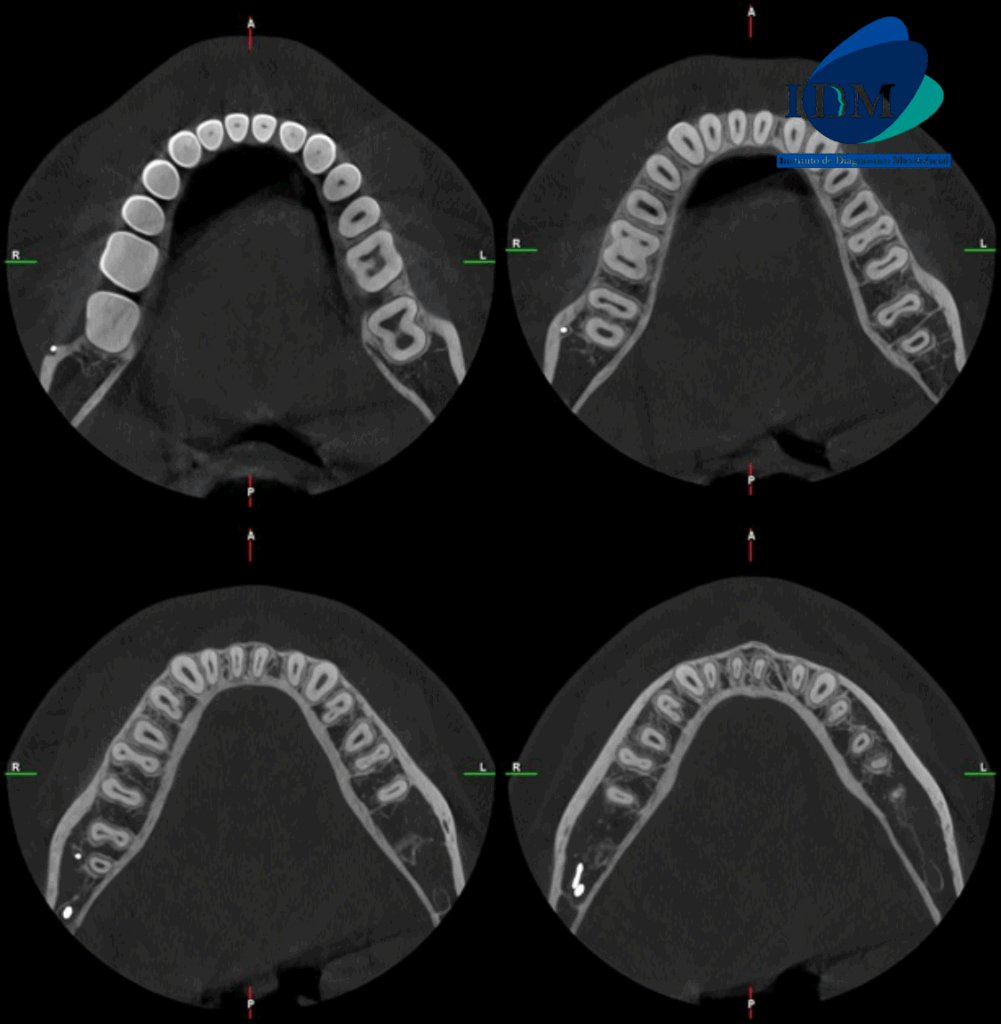

A la evaluación de la tomografía volumétrica (CBCT) en los cortes axiales (Figura 2) y transaxiales (Figura 3), se aprecia se aprecia bifurcación del conducto dentario inferior del lado derecho.

CORTES AXIALES

CORTES TRANSAXIALES